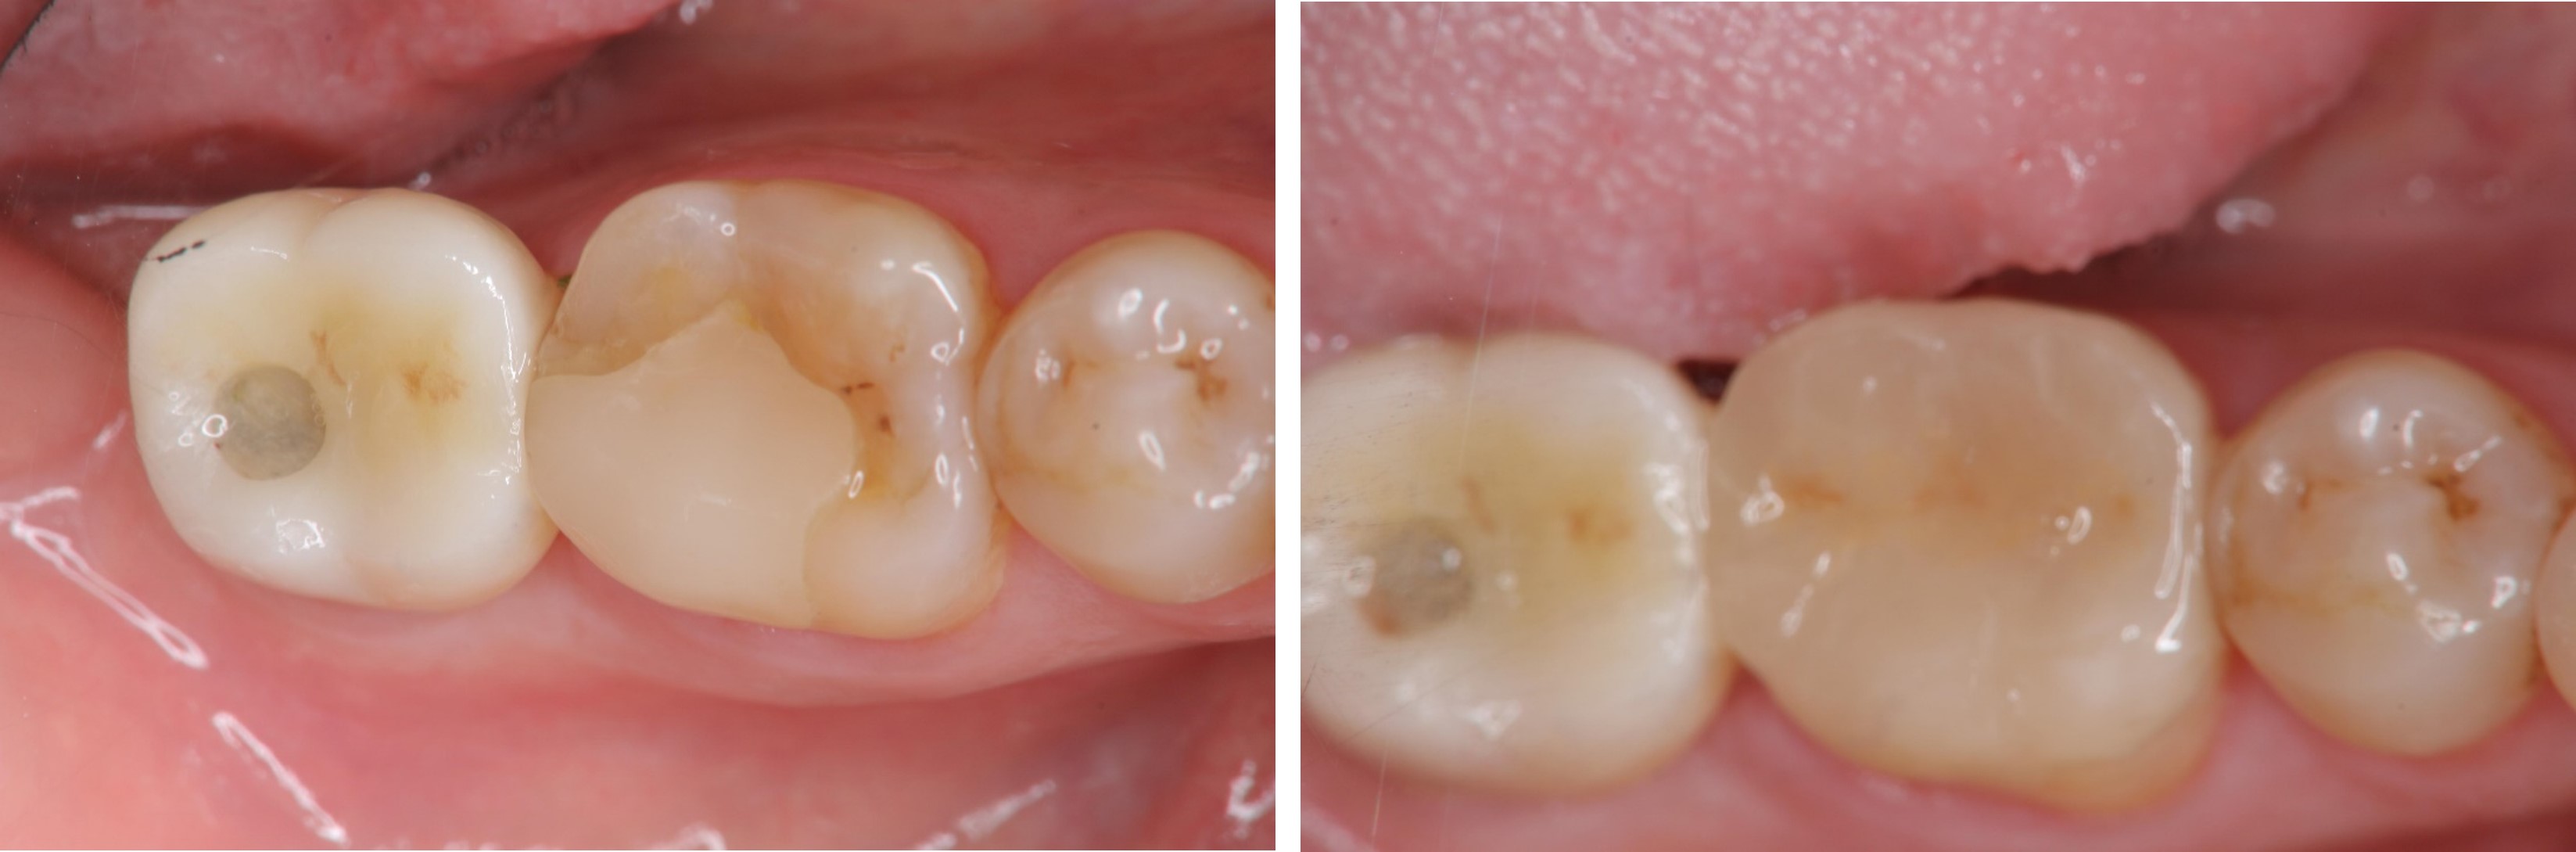

貼面邊緣完整

無殘膠存在

術前、術後比較